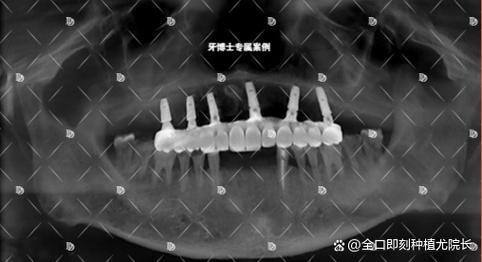

- 进行临床检查: 检查种植体周围牙龈的红肿、触痛、溢脓情况;检查咬合关系;轻轻叩诊种植牙看是否有疼痛;拍摄X光片(必要时)评估种植体周围骨组织情况。